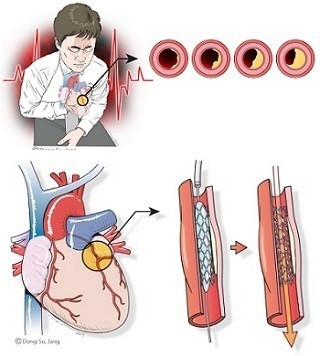

이는 심정지로 이어지는 응급 상황일 수 있으므로 즉시 119 또는 응급실로 이동해야 합니다.심근경색 주의사항

- 고혈압, 고지혈증, 당뇨병, 흡연, 비만, 가족력이 있는 분은 특히 위험군입니다.

- 증상이 5분 이상 지속되거나 반복되면 반드시 병원에 내원하세요.

- 심근경색은 갑작스럽게 오는 질환이므로 예방보다 초기 인지와 신속한 대응이 중요합니다.

- 심전도, 심장효소 검사, 심장 CT 등은 정확한 진단을 위한 필수 검사항목입니다.